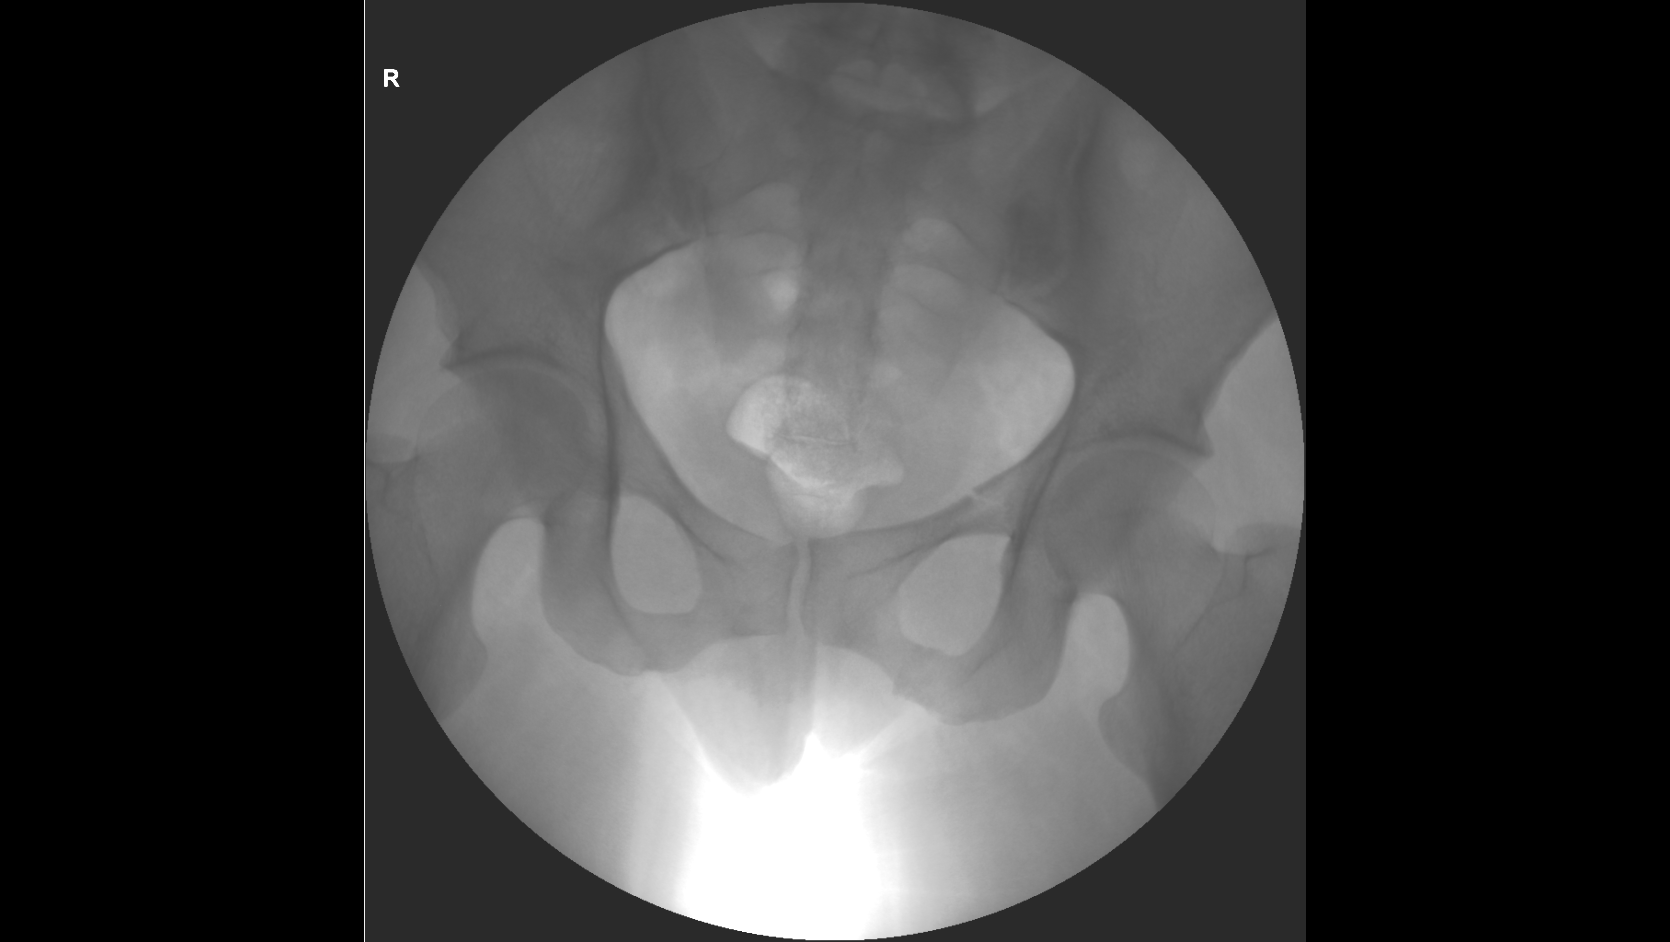

По вашей рекомендации я написал ходатайство о проведении повторной комиссионной экспертизы и сам в ней участвовал, так как разобрался с вашей помощью во всех деталях, практический, все включая следователя были уверены, что вред квалифицируют, как средней тяжести, но по результатам повторной экспертизы, каким то странным образом эксперты нашли еще один третий перелом правой лобковой кости, в результате чего вред здоровью стал действительно Тяжким.

Посмотрите, пожалуйста, третье заключение экспертизы, а то закрадывается сомнения о том, что смотрели три рентгенолага и установили три разных диагноза, и правильно ли они определили третий перелом.

Отправляю заключение комиссионной экспертизы и рентгенные снимки сразу после происшествия и по истечению двух месяце.

снимки сразу после аварии, через 2 месяца и через 3 месяца

Не могу разглядеть перелом правой лобковой кости, и, соответственно, 6.1.23.

На рентгенограммах хорошо видны переломы: правой лонной и правой седалищной костей, левой лонной кости. Перелома левой седалищной кости нет. "Условная граница" левой лонной и левой седалищной костей, на самом деле, находится на некотором расстоянии от места перелома левой лонной кости. Т.е. ссылка экспертов на прохождение линии перелома по этой условной границе представляется изрядно притянутой и, в любом случае, это непосредственно не свидетельствует о наличии перелома левой седалищной кости. Для оценки этой травмы как тяжкий вред нужен перелом типа "бабочки" всех четырех костей: правой лонной (он есть), правой седалищной (есть), левой лонной (есть), левой седалищной (нет!).

Убежден, что за такой перелом тяжкий вред давать неправильно. Это - вред здоровью средней тяжести (по п.7.1 вышеуказанного документа).

Путаница в сторонах переломов: на одном снимке противоположная сторона переломов верхней ветви лонной и ветви седалищной кости обозначена R, на остальных - L. Это может быть принципиальным. В остальном согласен: 6.1.23. отсутствует.